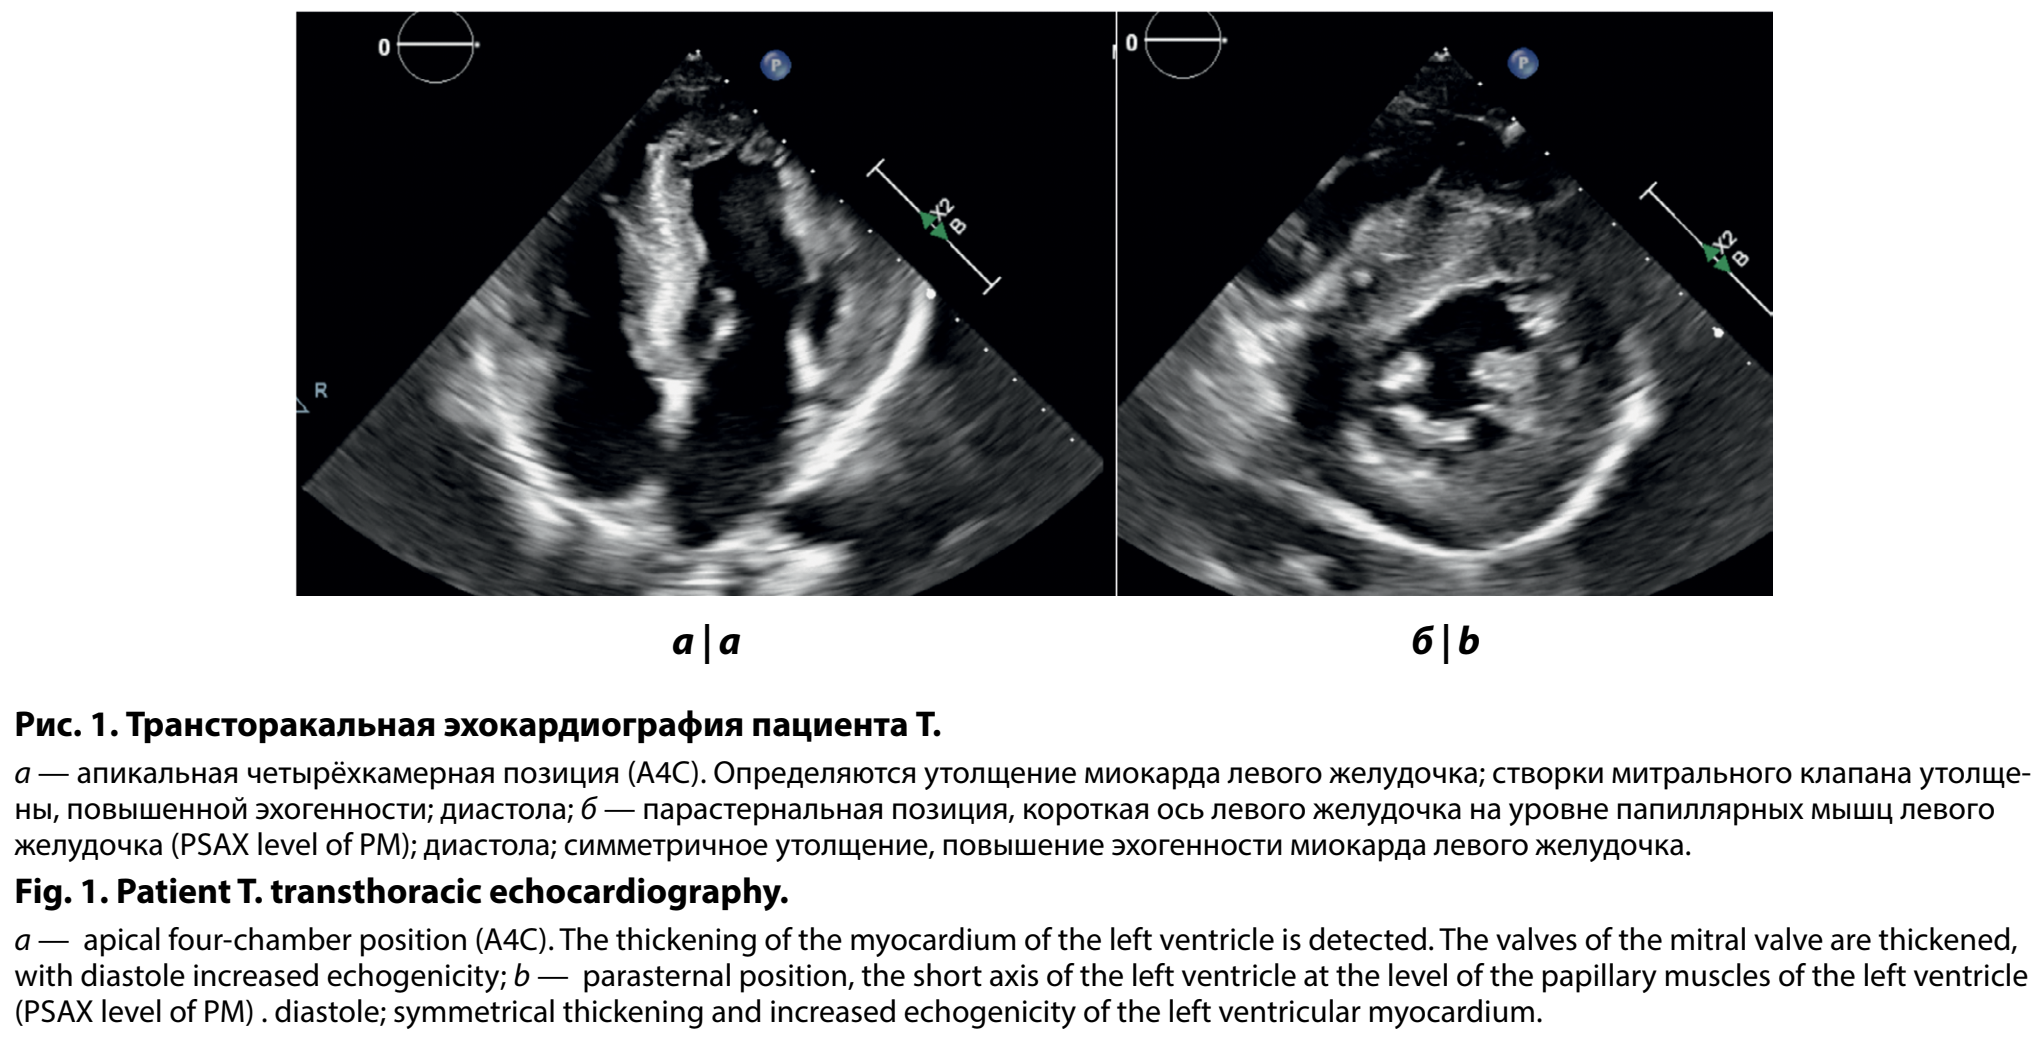

При клиническом осмотре в Центре в 11 лет обращало на себя внимание низкое, дисгармоничное физическое развитие за счёт дефицита массы тела (рост 133 см, вес 23 кг, индекс массы тела 13). Анализ лабораторных данных показал повышение уровня лактата в сыворотке крови до 3,7 ммоль/л (референсные значения — 0,5–1,6 ммоль/л), при этом исследование спектра ацилкарнитинов и аминокислот в сухих пятнах крови методом тандемной масс-спектрометрии патологии не выявило. По данным ЭхоКГ подтверждена гипертрофия межжелудочковой перегородки 17 мм и задней стенки левого желудочка 14 мм с минимальными признаками внутрижелудочковой обструкции (градиент 12 мм рт. ст.) и нарушением диастолической функции по 2-му типу (рис. 1).